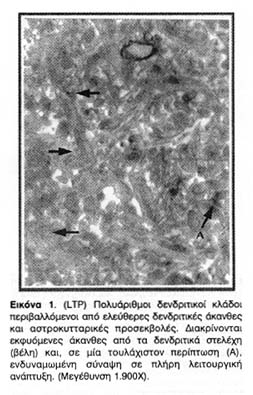

Το ηλεκτρόδιο διέγερσης τοποθετούνταν στην περιοχή των παράπλευρων κλωνίων του Schaffer (Schaffer collaterals) που περιέχει άξονες των πυραμιδικών νευρώνων της CA3 περιοχής του ιππόκαμπου. Τα ηλεκτρόδια καταγραφής, εξωκυττάρια και ενδοκυττάρια, τοποθετούνταν στην περιοχή της ακτινωτής στιβάδας (stratum radiatum) η οποία περιέχει πολλούς και πλούσια διακλαδωμένους δενδρίτες πυραμιδικών κυττάρων της CA1 περιοχής (Εικόνα 1).

Από τις φωτογραφίες ηλεκτρονικής μικροσκόπησης που ελήφθησαν παρατίθενται οι πλέον χαρακτηριστικές. Όλες προέρχονται από τη CA1 ιπποκαμπική περιοχή και συγκεκριμένα από την περιοχή που περιέβαλλε το σημείο της τοποθέτησης του ηλεκτροδίου καταγραφής δηλαδή μία περιοχή της ακτινωτής στιβάδας (stratum radiatum), η οποία περιέχει πολλούς και πλούσια διακλαδωμένους δενδρίτες πυραμιδικών κυττάρων της CA1 περιοχής (Εικόνα 1).

Οι φωτογραφίες χωρίστηκαν σε δύο ομάδες, στην πρώτη παρουσιάζονται οι νευρώνες ιπποκαμπικών τομών που είχαν δεχτεί ερέθισμα υψηλόσυχνης ριπής και είχαν ενδυναμώσει τη συναπτική τους απόκριση (LTP) (Φωτογραφίες 1-3) και στη δεύτερη οι νευρώνες ιπποκαμπικών τομών που είχαν δεχτεί ερέθισμα χαμηλόσυχνης ριπής και είχαν αποκτήσει αποδυναμωμένη απόκριση (LTD) (Φωτογραφίες 4-6). Μέσα σε κάθε ομάδα οι φωτογραφίες έχουν διαταχθεί συνήθως σε σειρά αυξανόμενης μεγέθυνσης ώστε να γίνει ευκολότερη και σαφέστερη η παρουσίαση των δομικών μεταβολών που παρατηρήθηκαν.

Τέλος, χρησιμοποιήθηκαν βέλη με γραμματοσήμανση ως βοηθήματα παρουσίασης των παρατηρήσεων που αναγράφονται στα υπομνήματα των φωτογραφιών για ακριβέστερη περιγραφή. Τα συμπεράσματα των παρατηρήσεων συνοψίστηκαν μετά την παρουσίαση των φωτογραφικών δεδομένων και η σημασία τους αναλύεται στη συζήτηση όπου παρατίθενται και τα σχετικά συμπεράσματα. Η εξαγωγή συμπερασμάτων από τη μελέτη φωτογραφιών ηλεκτρονικής μικροσκοπίας συνοδεύεται πάντα από τον κίνδυνο, μοναδικές παρατηρήσεις να αναχθούν σε γενικευμένα συμπεράσματα. Όταν όμως το ίδιο φαινόμενο καθίσταται επανειλημμένα αντιληπτό σε μεγάλο αριθμό δειγμάτων, τότε οι παρατηρήσεις αντικατοπτρίζουν ένα πραγματικό φαινόμενο και η μελέτη κάτω από το ηλεκτρονικό μικροσκόπιο επιτρέπει τον εντοπισμό λεπτομερειών που θα διέφευγαν με μελέτη διαφορετικής προσέγγισης.

Κοινό χαρακτηριστικό των συνάψεων των ενδυναμωμένων νευρώνων είναι η αύξηση όχι μόνο της συνολικής συναπτικής επιφάνειας αλλά και της λειτουργικής μετασυναπτικής επιφάνειας της μετασυναπτικής πύκνωσης (PSD), η οποία φαίνεται ως ηλεκτρονιακά πυκνή (σκουρόχρωμη) πάχυνση της μετασυναπτικής μεμβράνης και η οποία αντιστοιχεί σε μεμβρανική περιοχή πλούσια σε υποδοχείς και διαύλους οργανωμένους σε κβαντικές δέσμες.

Όπως φαίνεται από τις φωτογραφίες 1, 2 και 3 η πρόκληση LTP οδηγεί τις άκανθες, των οποίων οι συνάψεις ενδυναμώνονται, να διογκωθούν, και να αυξήσουν έτσι την αποτελεσματικότητα των συνάψεων τους, με την προέκταση της λειτουργικής επιφάνειάς τους. Επιπλέον, οι φωτογραφίες αυτές είναι ενδεικτικές της δενδριτικής ανάπτυξης νέων κλάδων και ακανθικών προεκβολών που προκαλείται από την ενδυνάμωση των ιπποκαμπικών συνάψεων. Αυτές οι παρατηρήσεις, βέβαια, απλώς επιβεβαίωσαν παλαιότερα συμπεράσματα για τις δομικές και ανατομικές μετατροπές που επιφέρει η πρόκληση LTP στους δενδρίτες της CA1 περιοχής του ιππόκαμπου και ήταν ήδη γνωστές από παλαιότερες εργασίες.